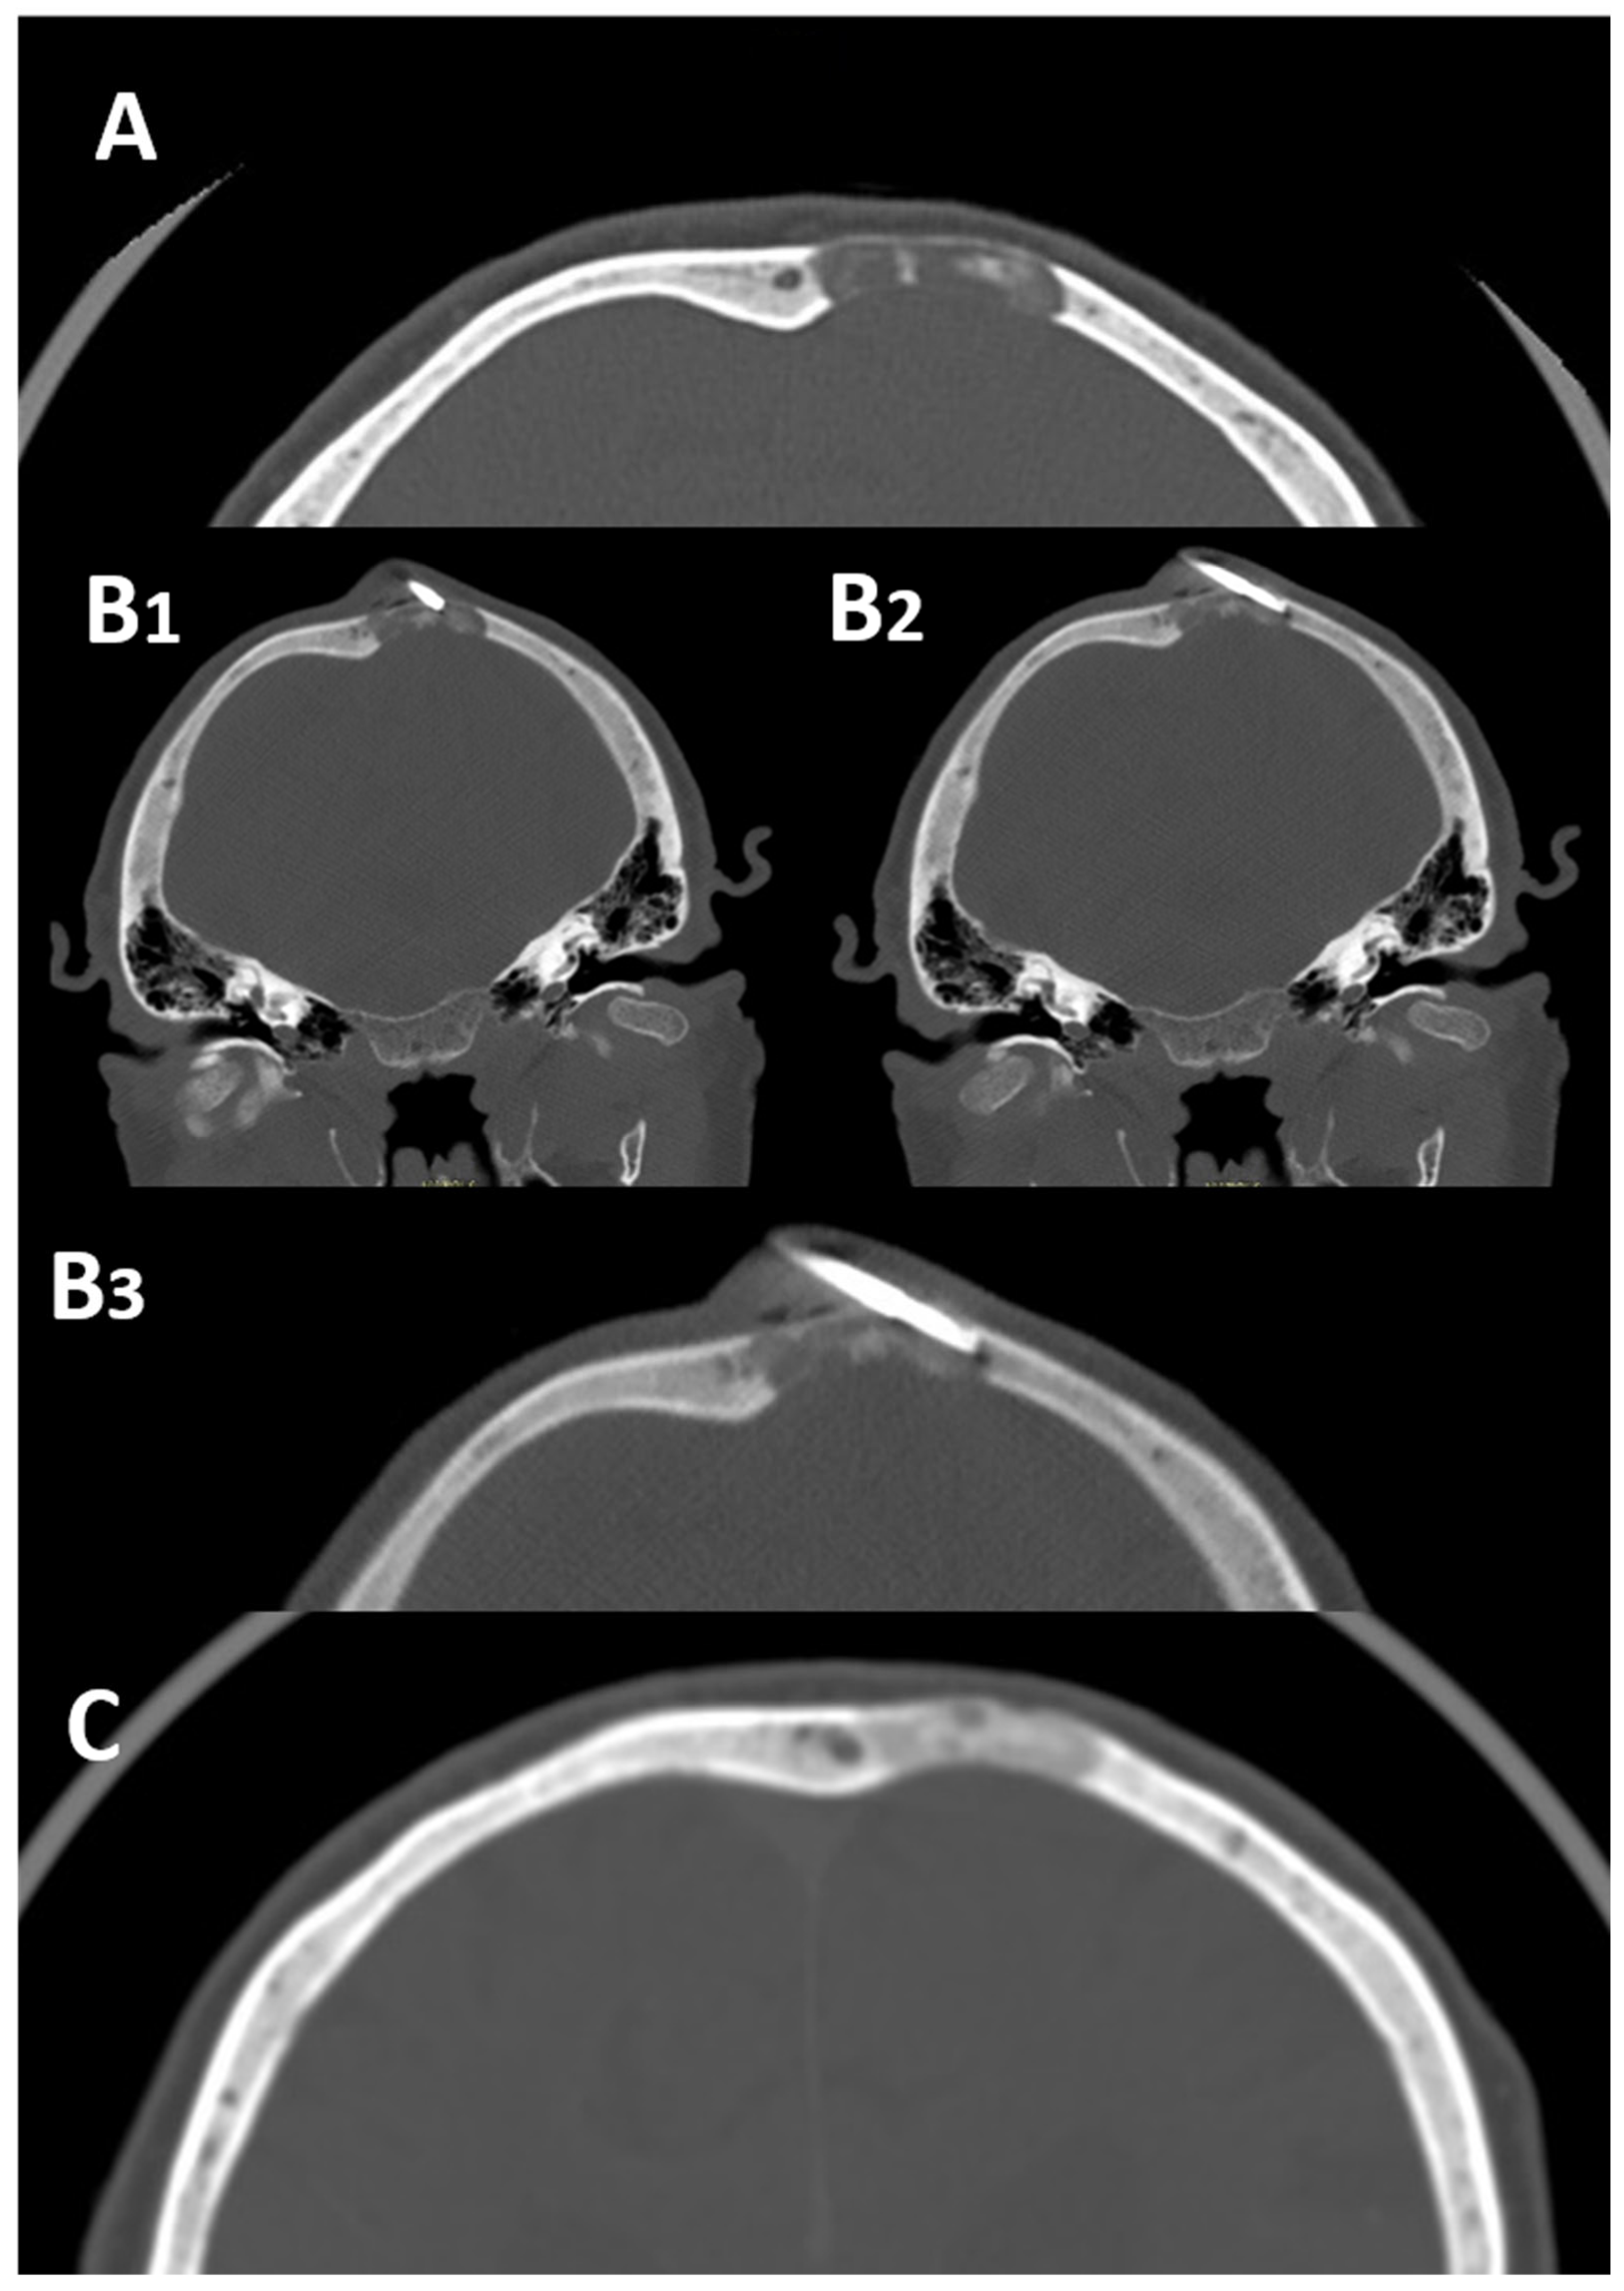

2.1. Skull

- Tomasian, A.; Hillen, T.; Jennings, J. Percutaneous CT-Guided Skull Biopsy: Feasibility, Safety, and Diagnostic Yield. Am. J. Neuroradiol. 2019, 40, 309–312. [Google Scholar] [CrossRef]

- Sundararajan, S.H.; Cox, M.; Sedora-Roman, N.; Ranganathan, S.; Hurst, R.; Pukenas, B. Image-Guided Percutaneous Calvarial Biopsy with Low-Dose CT-Fluoroscopy: Technique, Safety, and Utility in 12 Patients. Cardiovasc. Interv. Radiol. 2022, 45, 134–136. [Google Scholar] [CrossRef]